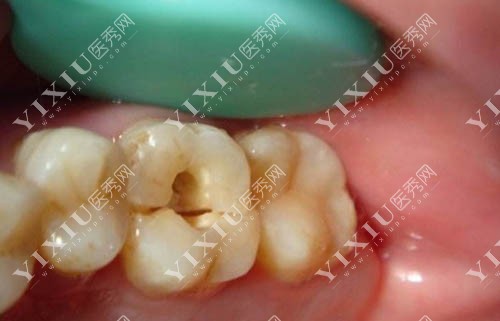

龋坏清理后照片

z250系列适合前牙修复,术后美观度更高,看起来也比较自然,补牙后也几乎看不出来手术痕迹。

牙齿龋坏照片